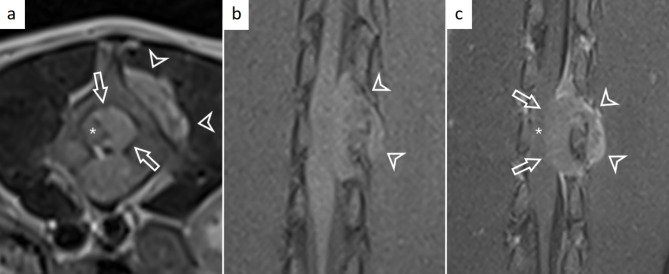

Case presentation: This case report describes a 10-week-old female Rottweiler puppy with acute onset of progressive ataxia and pelvic limb lameness. Neurological examination localised a T3-L3 myelopathy and MRI revealed an ovoid, well-marginated mass extending from mid L3 to caudal L4 vertebrae. Post-mortem examination, histopathology, and immunohistochemistry confirmed a round cell sarcoma of extradural origin.